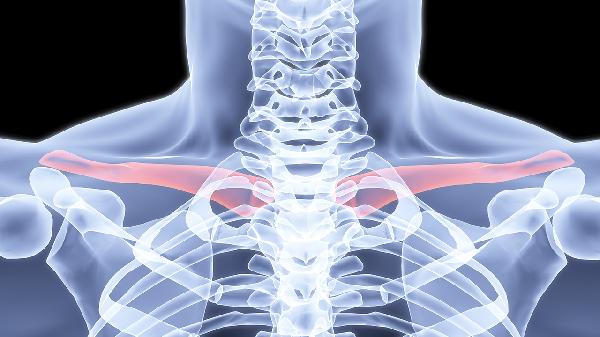

鎖骨骨折保守治療要多少錢

鎖骨骨折保守治療一般需要2000元到8000元,實際費用受到骨折類型、治療方案、地區(qū)差異、復(fù)查頻率、并發(fā)癥處理等多種因素的影響。